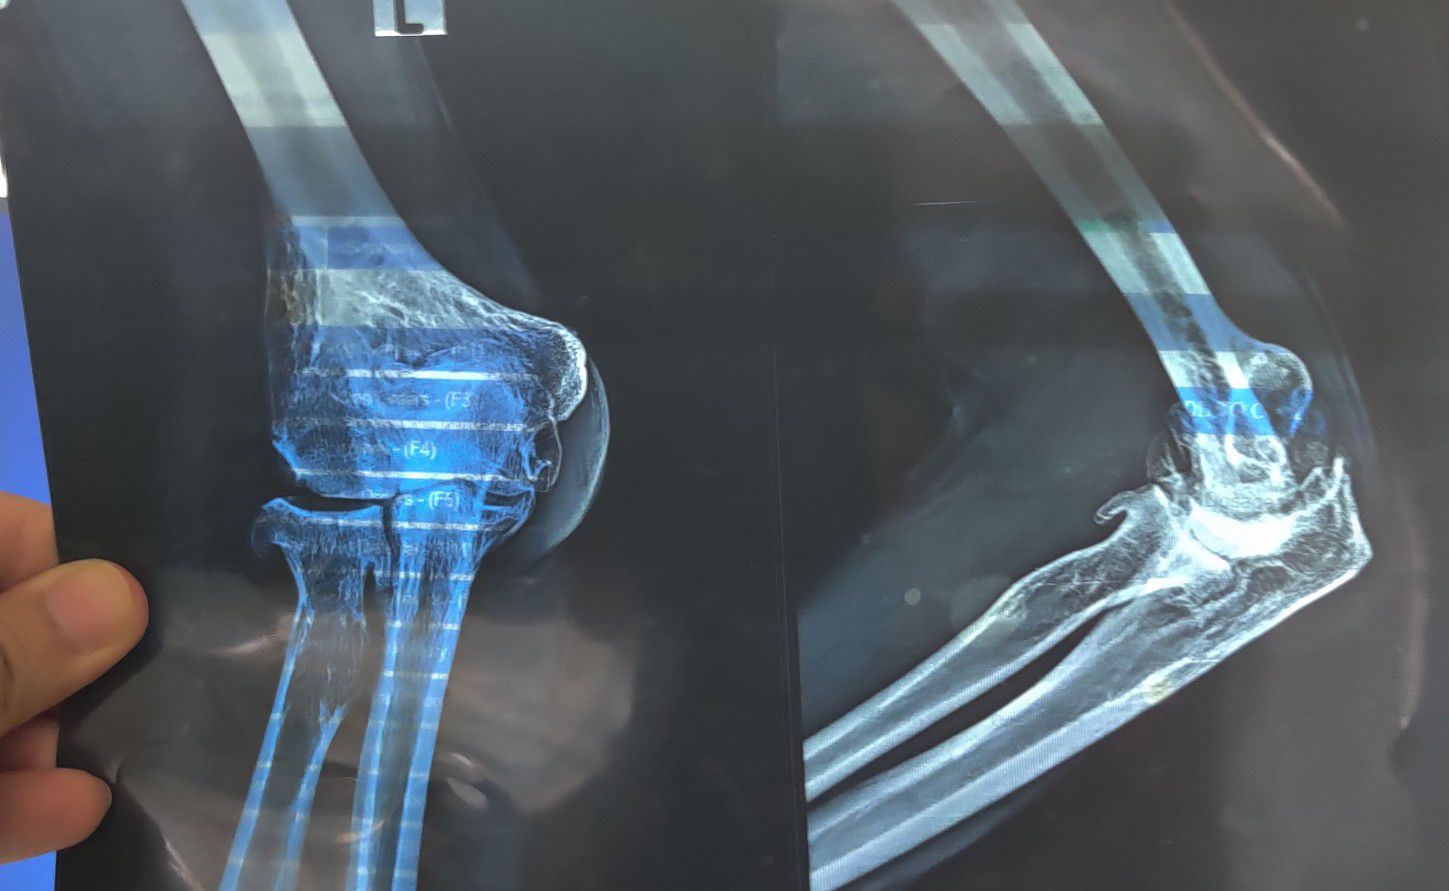

Old Fracture of L Elbow

Ortho

Elbow

Fractured